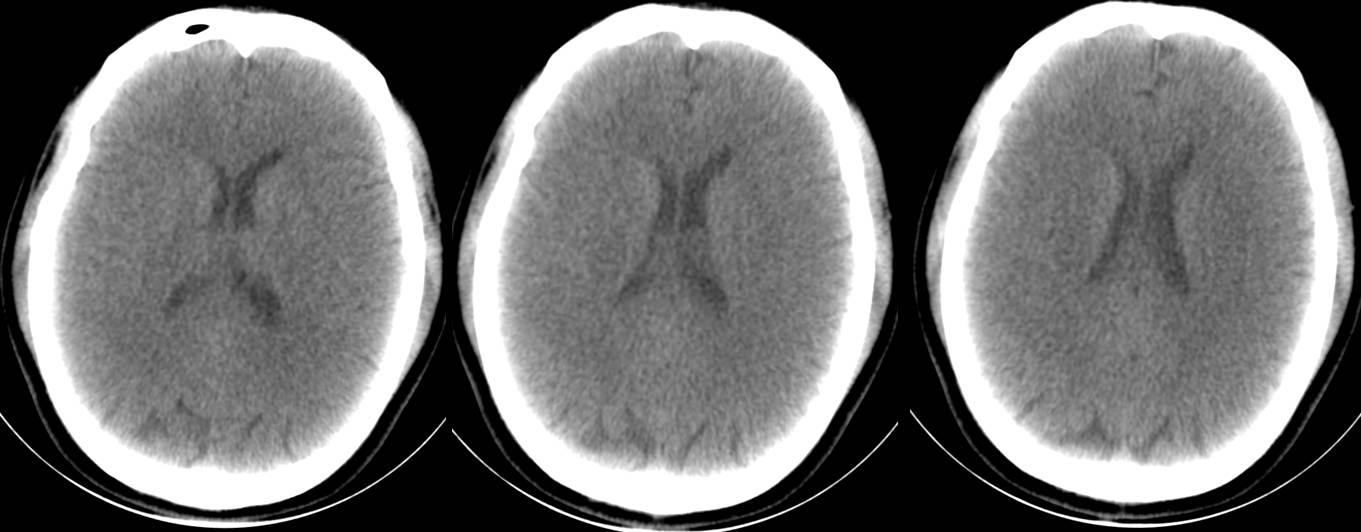

16层CT头部扫描(正常志愿者)

16层移动CT脑部扫描